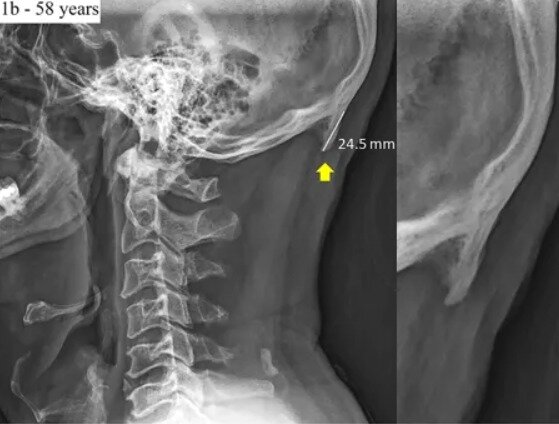

스마트폰이 두개골 구조 바꾼다…어떻게?

두개골 아래쪽 뼈 두툼해져…하중 버티려고 뼈 키워

본문 이미지 - 네이처닷컴 화면 갈무리ⓒ nature.com

네이처닷컴 화면 갈무리ⓒ nature.com